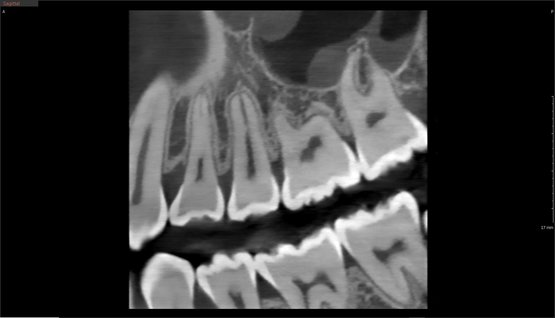

Das Green X ist ein 4-in-1 Röntgenbildgebungssystem der Superlative, welches sowohl 2D-Modalitäten wie Panorama- und kephalometrische Aufnahmen in ultrahochauflösender Bildqualität ermöglicht, als auch flexible 3D-DVT-Aufnahmen von Patienten, Modellen und Abformlöffeln.

• Endo Modus mit höchster Auflösung FOV 4x4; Ultra-High-Resolution 49µm; 3,5 Lp/mm

• Free FOV Insight PAN 2.0 Multilayer mit 41 Schichten

Das Green X ist mit 49μm bei einem FOV von 4x4 cm das Gerät mit einem der weltweit höchsten Auflösungen und der daraus resultierenden Detailschärfe. Dank der byzzEz3D-i Software mit dem Endo-Modul rekonstruiert diese aus ultrahochauflösenden Schichtaufnahmen perfekte 3D Aufnahmen. Diese können dann als Hologramm in allen drei Dimensionen vermessen werden.

Eine von vielen Besonderheiten des Green X ist die erweiterte Insight PAN 2.0 Funktion.

Das Insight PAN 2.0 Scan Protokoll (mit 41 Schichten im Multilayer) erlaubt Ihnen Panorama-Aufnahmen für mehr Tiefenschärfe. Diese Funktion begrenzt die Mehrschichtaufnahmen auf die Region, welche durch das Free FOV festgelegt wird. Somit wird die Dosis für den Patienten maximal reduziert und ermöglicht erstmalig Multilayer-Zahnfilm- und Multilayer-Bissflügel-Aufnahmen.

Green X von orangedental 2D Aufnahme